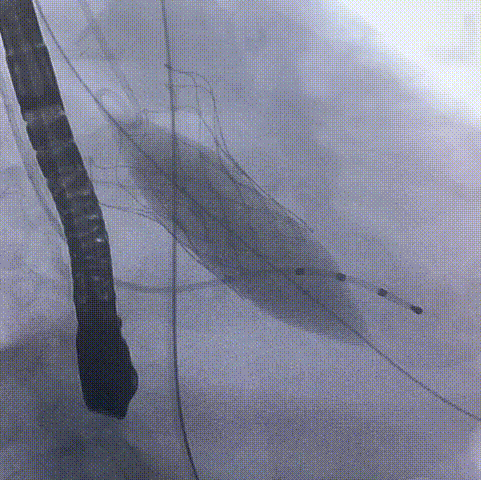

术中过程

窦部造影

导丝跨瓣

球囊预扩

瓣膜定位

瓣膜开始释放

瓣膜完成释放

球囊后扩

瓣膜形态良好,

无周漏

术后伤口缝合

术后造影及超声探查未见瓣周漏,血压改善,术后几乎无压差,术中及术后均未出现相关并发症,仅用时不到一小时手术圆满完成。